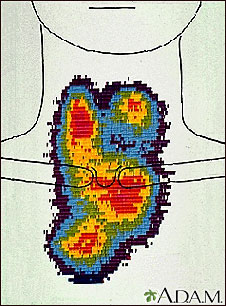

After the surgery, you may receive radioiodine therapy, which is often taken by mouth. This substance kills any remaining thyroid tissue. It also helps make medical images clearer, so doctors can see if there is any cancer left behind or if it comes back later.

- An imaging test called a radioactive iodine (I-131) uptake scan